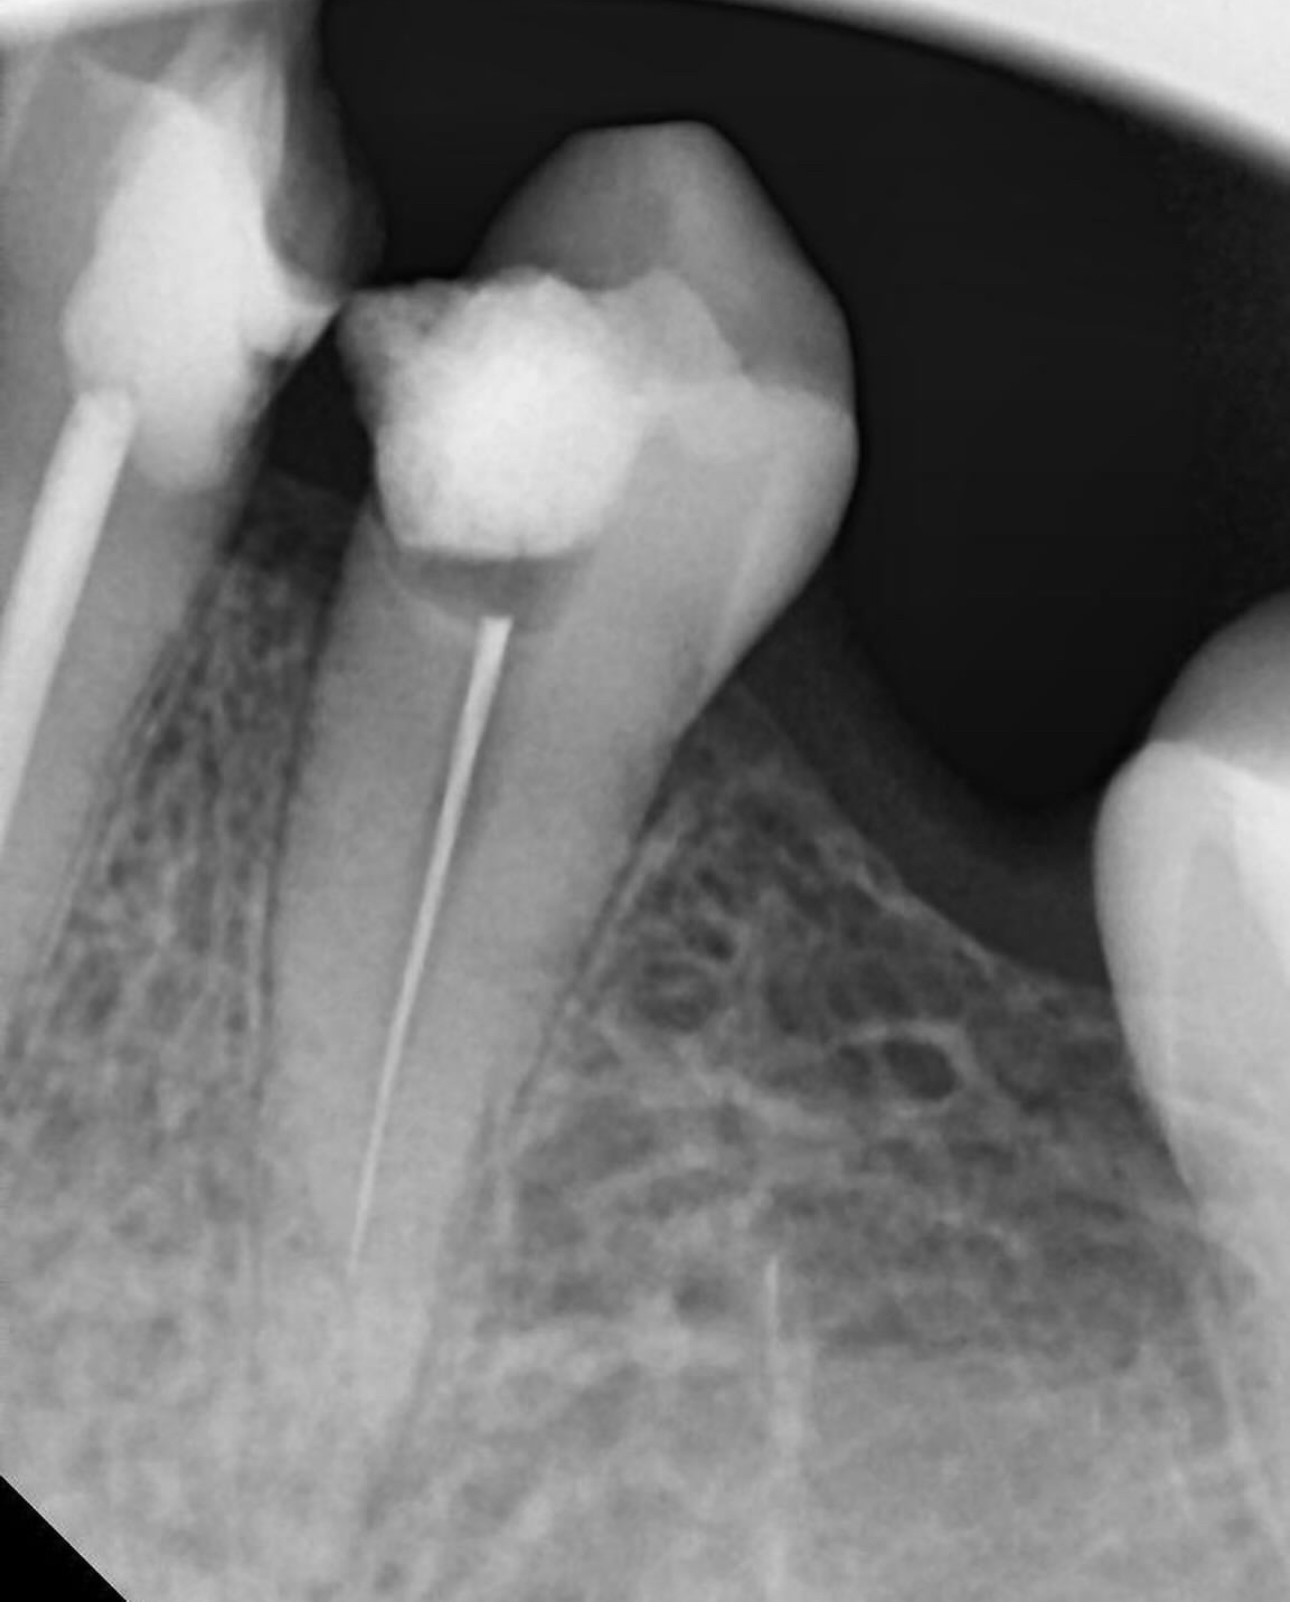

25. What option can be selected for RCT of tooth # 1.4?

26. What option can be selected for the tooth # 3.6?